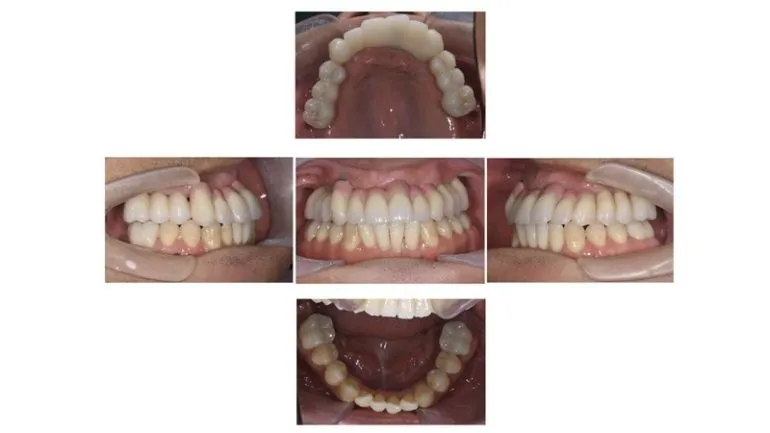

【症例1】

治療名

インプラント治療

治療説明

インプラント治療とその他の補綴物による修復を行いました。

治療期間

1年

副作用・リスク

手術中に神経や血管を傷付ける可能性があります。痛み、腫れ、出血があります。インプラントの初期固定が取れない場合は、治療期間が長引いたり、すぐに仮歯を装着できない場合があります。

料金

¥3,135,000(税込)

インプラントのみ